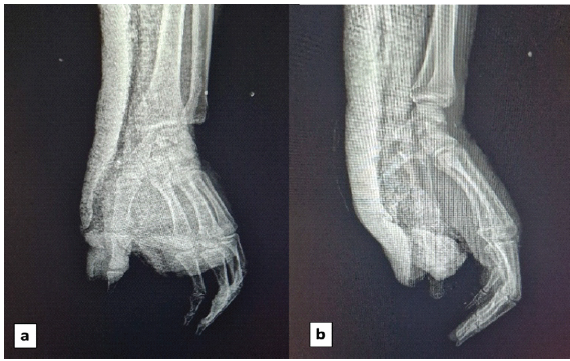

Immediate post-operative radiographs were satisfactory (Fig. 4). Complete wound healing was achieved by day 12, and the anterior plaster cast was removed 45 days post-injury.

Figure 4: immediate post-operative radiographs. (a) Anteroposterior and lateral (b) views confirming stable reduction of the carpometacarpal and interphalangeal dislocations after closed reduction and immobilization with an anterior splint including the thumb column.